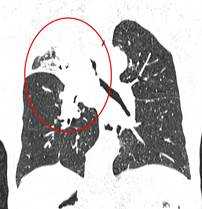

КТ-признаки центрального рака легкого: при компьютерной томографии определяется объемное образование мягкотканной структуры, в котором «обрывается» просвет нижнедолевого бронха. Края образования бугристые, неровные, со спикулами, форма неправильная.

Центральный рак легкого на КТ. Обратите внимание на различия в ширине просвета центральных бронхов справа и слева. Просвет правого верхнедолевого бронха не виден. Виден ателектаз верхней доли. В круге - непосредственно само опухолевое образование, ставшее причиной ателектаза.

Периферический рак легких на КТ выглядит как очаг либо узел, расположенный на периферии органа вдалеке от корня. Обычно он имеет однородную структуру, в некоторых случаях с участками некроза, обызвествлениями и кровоизлияниями в паренхиму. Края типичной раковой опухоли неровные, с множественными «спикулами» за счет лимфангиита. При расположении вблизи плевры образование деформирует ее и подтягивает к себе. Размеры его различны - от очага (3-10 мм) до узла (10-50 мм и больше).

Типичный периферический рак легкого (аденокарцинома) на МСКТ. Справа в 6 сегменте легкого выявлен плотный мягкотканный узел со спикулами, деформирующий и подтягивающий к себе междолевую плевру.